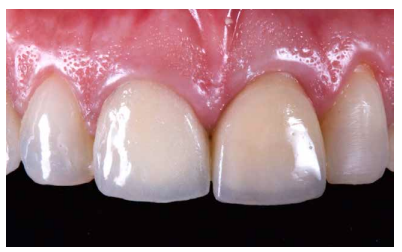

Se presenta el caso clínico de una mujer de 52 años de edad, que acudió a la consulta odontológica debido al descementado de una corona metal-cerámica dentosoportada en el diente 2.1 (ICSI) (Figuras 1-3). La paciente refería una alta preocupación por su estética.

Utilizando el escáner 3Shape®, se realizó un pre-escaneado intraoral, primero con la corona dentosoportada colocada, para obtener la anatomía del incisivo central, y después sin ésta, escaneando así el perfil de emergencia del resto radicular; se informó al laboratorio de la modificación del perfil critico, corrigiendo así la recesión existente respecto al 1.1 (Figuras 5-7). Este escaneado sirvió a su vez para la toma de color del futuro provisional7,8. El archivo STL fue enviado al laboratorio protésico para elaborar la prótesis provisional tipo Maryland, en polimetil-metacrilato (PMMA), con dos apoyos en los bordes incisales de los dientes adyacentes para asegurar su correcto posicionamiento que, según la planificación previa, serviría como diente provisional, así como de guía quirúrgica para la inserción del IOI en la posición protésica idónea, evitando así posibles problemas futuros a nivel protésico o en la integridad de los tejidos blandos y duros de la región vestibular (Figuras 8 y 9).